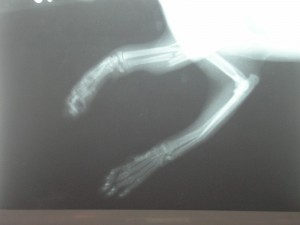

Sisi byla nalezena 29.03.2006 na sídlišti s polámanými předními packami. Utrpěla fraktury obou předních končetin, z nichž jedna byla tříštivá fraktura loketní a vřetenní kosti, došlo také ke zdevastování měkké tkáně.

Sisi RTG před